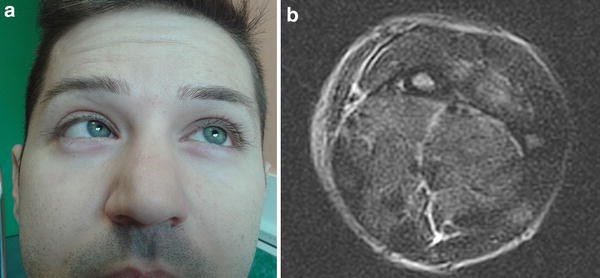

A 28-year-old man presented with fever, myalgia and swelling of the left forearm. The history was remarkable for cystic fibrosis, pulmonary and renal transplants complicated by rejection, compensated diabetes mellitus, and hemodialysis fistula on the left forearm. Two days later, the fever disappeared, but the patient complained of sudden onset diplopia and left ocular pain. Neurologic examination revealed a left abduction deficit, consistent with left abducens nerve palsy (Fig. 1a).

Clinical presentation: left abducens nerve palsy (a). Axial T2-BLADE MRI image of the mid left forearm shows diffuse swelling and hyperintensity of the muscles and subcutaneous tissue consistent with inflammatory oedema (b)

Pharmacologic history included mycophenolate mofetil, tacrolimus, prednisone, antihypertensive drugs, and insulin. Blood studies showed high CRP (9.38 mg/dl; n.v. <0.5) and procalcitonin (95.56 ng/ml; n.v. 0.002–0.06). Blood cultures were negative. Treatment with daptomycin 6 mg/kg/day every other day and meropenem 1 g/day was started. Viral and antibody testing were negative. A brain MRI without contrast was normal. T2-weighted MRI of the left forearm revealed hyperintensity of the muscular and subcutaneous tissues, consistent with inflammatory edema (Fig. 1b). Two weeks later, blood studies showed normal CRP (0.42 mg/dl; n.v. <0.5) and near normal procalcitonin (2.57 ng/ml; n.v. 0.02–0.06). Six weeks later, ocular motility was normal, and an MRI of the left forearm showed reduction of muscle edema. The sixth cranial nerve (abducens nerve) innervates the lateral rectus muscle, which is responsible for abducting the eye [1]. Abducens nerve palsies occur more frequently in children while they are unusual in young adults [2, 3]. The leading causes of acquired abducens nerve palsy are neoplasm and trauma [2, 4]. Inflammatory palsies are less frequent and can recover after appropriate treatment, as was the case in our patient [2].